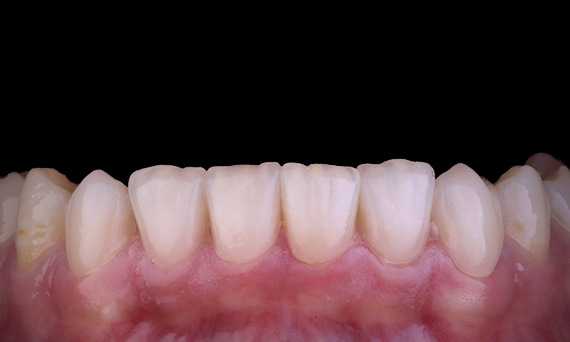

Bei Amalgamfüllungen sind häufig Risse und Frakturen zu beobachten, vor allem, wenn sie größer werden, da es sich um „unverbundene“ Restaurationen handelt. Viele dieser Zähne sind strukturell geschädigt, und ein adhäsiver, biomimetischer Ansatz ist die ideale Methode zur Restauration dieser Zähne. Als Teil eines umfassenderen Behandlungsplans sollten in diesem Quadranten zwei indirekte Keramik-Onlays eingesetzt werden. Die ersten und zweiten Molaren wurden während einer einzigen Sitzung mit CEREC Tessera, einem modernen Lithium-Disilikat, restauriert.

Dr. Sahil Soni, Queensland, Australien